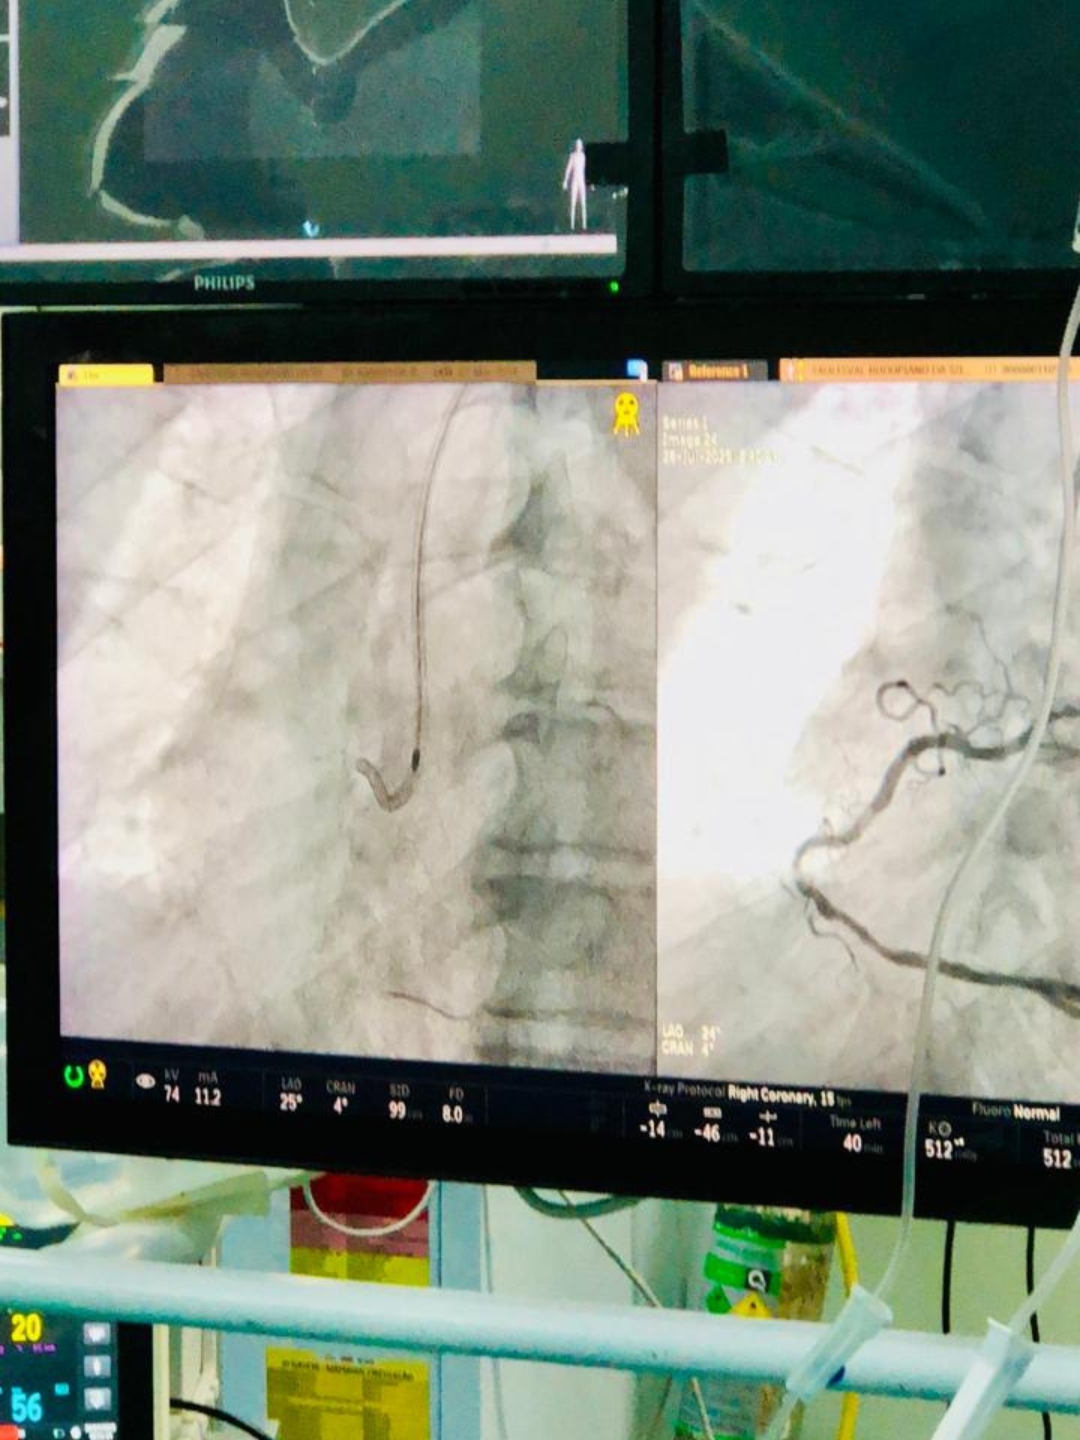

O Hospital Metropolitano Dom José Maria Pires, gerenciado pela Fundação Paraibana de Gestão em Saúde (PB Saúde), realizou na última segunda-feira (28), um procedimento de angioplastia coronária com Aterectomia Rotacional, utilizando um dispositivo conhecido como Rotablator. A intervenção inédita na unidade foi fundamental para um idoso de 71 anos que apresentava calcificação severa em uma artéria do coração, impossibilitando métodos convencionais de angioplastia.

De acordo com o médico cardiologista intervencionista Thiago Lisboa, o paciente já havia sido internado há cerca de um mês, quando tentaram realizar a angioplastia convencional, com balão e stent, sem sucesso, devido à extrema calcificação. A aquisição do material necessário, que é extra-SUS, foi solicitada pelo hospital para garantir o êxito do procedimento, marcando um avanço significativo na capacidade de tratamento de casos complexos na instituição.

A aterectomia rotacional permite a remoção ou redução da placa calcificada que obstrui a artéria, abrindo caminho para a colocação do stent e o restabelecimento do fluxo sanguíneo adequado.